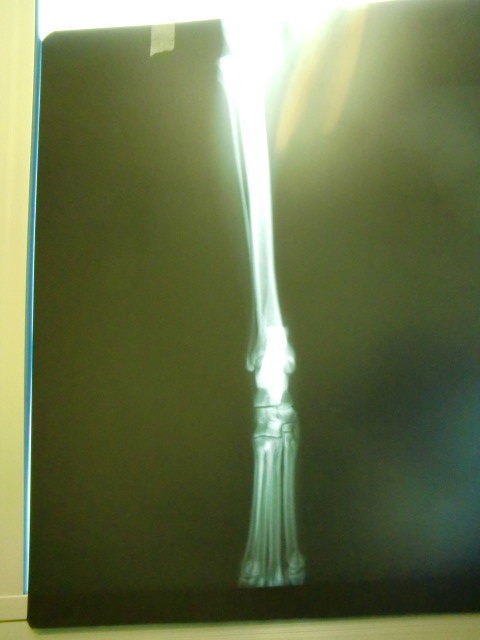

すぐに駆け寄り状態を見るも右後ろ足をかばっていて歩けるような状態ではなくもはや素人には分かる範疇ではなくすぐに病院へ。

触診では「恐らく前十字靱帯損傷で折れてはいないと思うけど分からない」とのことだったのでレントゲンもお願いしたところやはり前十字靱帯断裂が濃厚に。

前十字靭帯断裂

体重11.3kg

再診料 500

レントゲン 5000

薬処方(リマダイル 3T) 1000

---------------------------

合計 ¥6500-